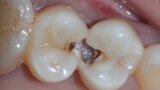

Predictable posterior restorations